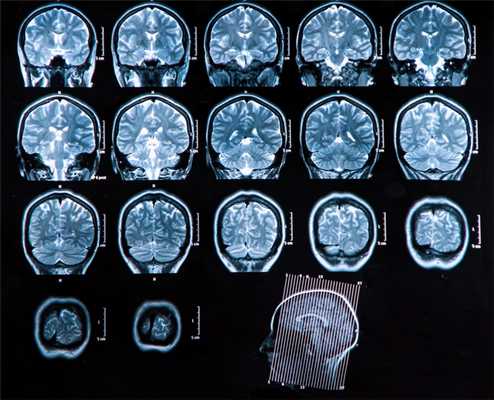

МРТ — головной, спинной мозг, молочные железы, связки и мышцы, органы малого таза и другие мягкотканные структуры.

Головной мозг

Основной метод оценки непосредственно вещества головного мозга (в том числе первичных опухолей и метастазов) — МРТ с применением контрастного усиления.

Компьютерная томография используется как дополнительный метод в случае, если требуется оценка состояния костных структур, а также при наличии абсолютных противопоказаний к МРТ исследованию (наличие металла в теле — например, кардиостимулятора, ферромагнитных инородных металлических соединений: пластины, протезы, импланты и т.п.)

Спинной мозг

Основной метод диагностики опухолей в спинном мозге — МРТ с контрастом. Он позволяет определить локализацию патологического процесса (интрамедуллярный или экстрамедуллярный, то есть находящийся в структуре спинного мозга или вне его), оценить его распространённость, вовлечение соседних структур. Если есть противопоказания к МРТ, а также, когда нужно детально разобраться с состоянием расположенных рядом позвонков, проводят КТ.